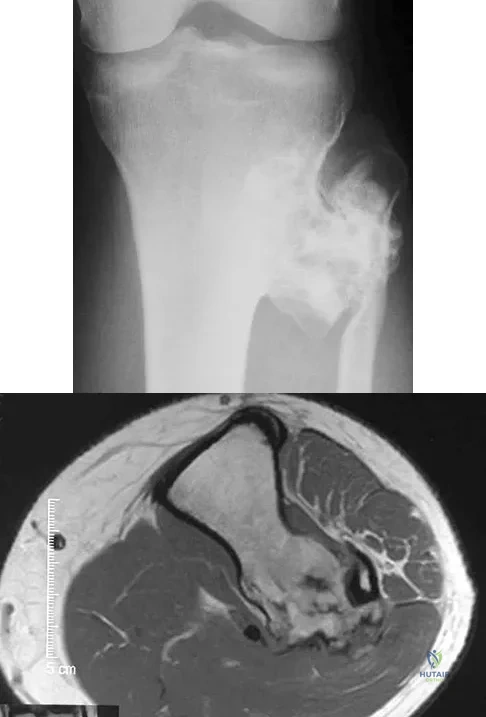

A 24-year-old man has had pain in the left knee for the past several months. He reports that initially the pain was associated with weight-bearing activities, but it has now become more constant. He denies any swelling but reports a lateral fullness at the tibial plateau. Figures 23a through 23e show radiographs, a bone scan, and T1- and T2-weighted MRI scans. What is the most likely diagnosis?

Explanation